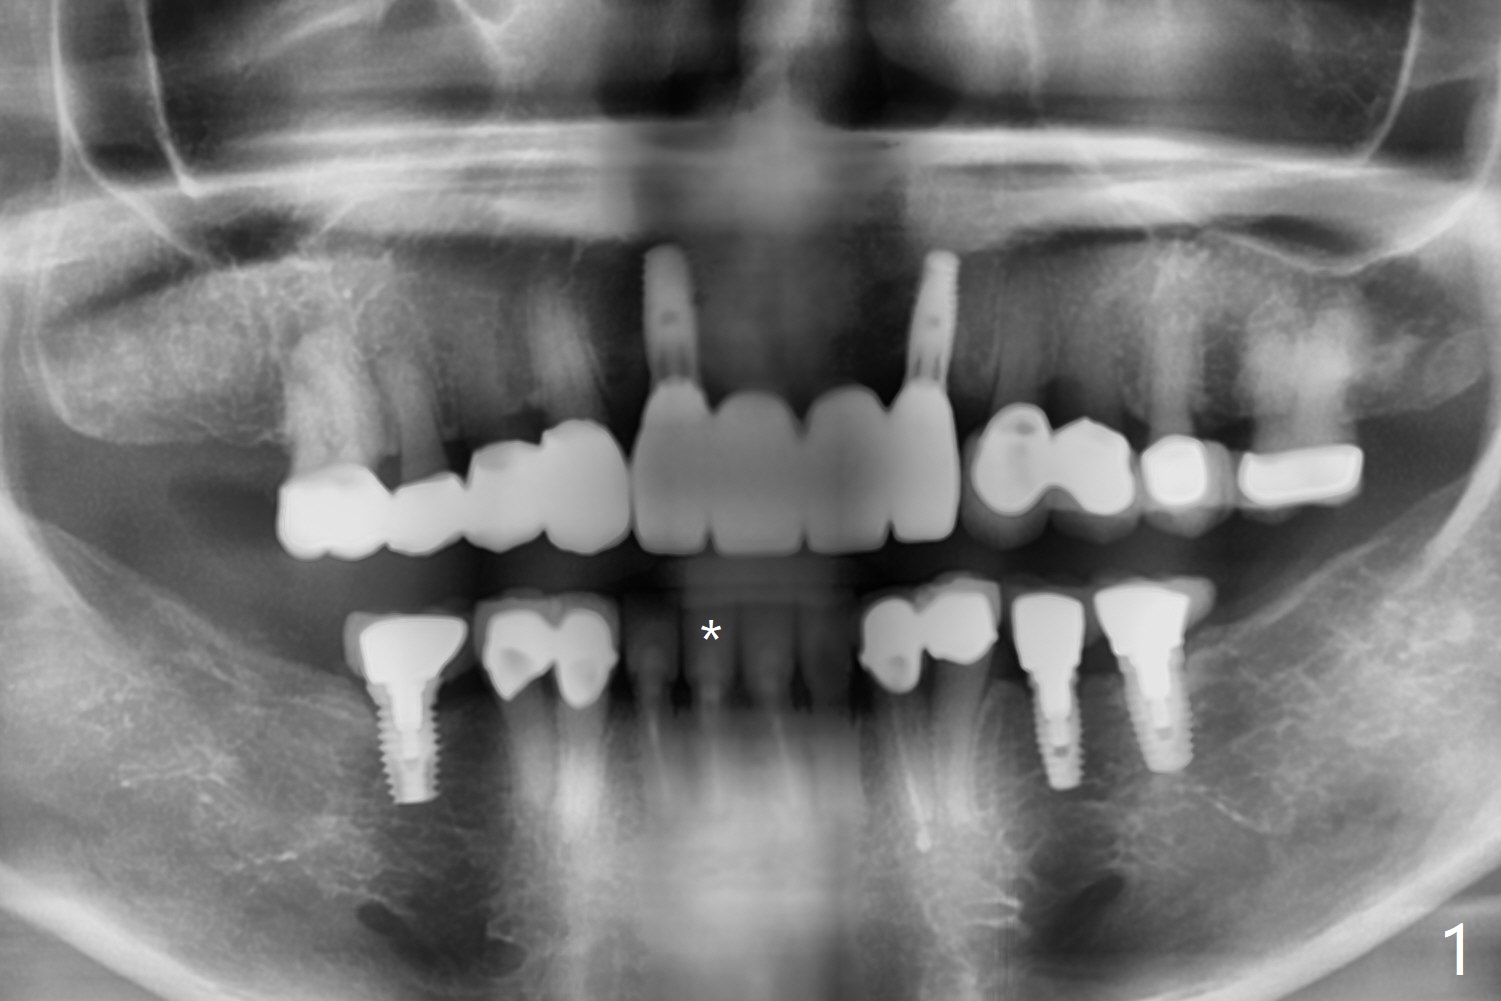

2.5x14(2) mm Implant

A 75-year-old woman with history of full mouth reconstruction requests implant for the tooth #25 with horizontal fracture with PARL (Fig.1-3).